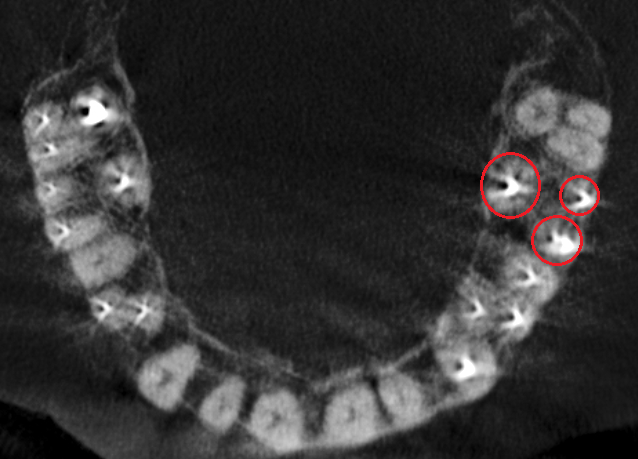

Контрольная ортопантомограмма:

Прицельный снимок:

Я согласен, что эстетика хромает. Давно пора менять временную коронку на постоянную, что улучшит результат. Но, как я говорил, все упирается в финансы.